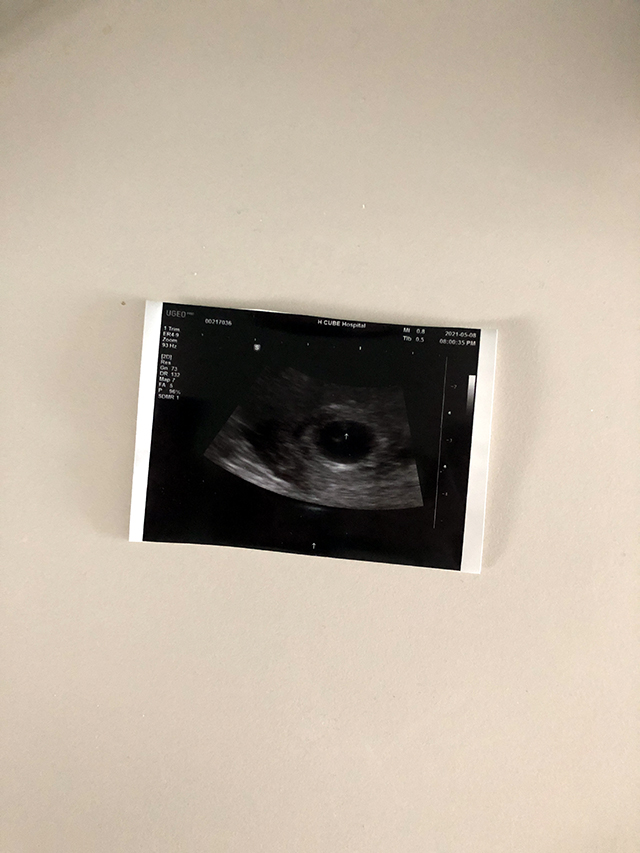

그리고 그냥 급 산부인과 가서 초음파를 보기로 했다.

원래 다음주 화요일에 둘다 반차내고 갈까 했는데 뭐 굳이?

몇 번 가봤던 산부인과가 토요일 오후 4시까지 하길래 찾아갔다.

접수하고, 진료실 들어가는 거 기다리는 중! 오빠가 떨린다며 헤헤

대략 6주정도 됐다고 했다. 착상 위치도 좋고 난황도 보여주셨다.

심장소리는 아직 잘 들리지 않았지만 아주 작게나마 들려주셨다.

살짝 피 고임이 있는데 이건 그냥 푹 쉬면 사라진다고 하셨다. 걱정 노노!

담당 선생님도 좋으셨고, 병원 위치도 가까워서 마음이 한결 가벼웠다.

초음파 사진도 친절하게 세 장 뽑아주셨다 흐흐 이걸로 양가 부모님께 임밍아웃 할 생각!